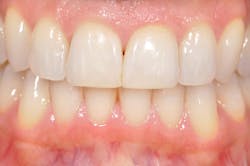

Figure 2: Prior to procedures, teeth appeared healthy with no clinical signs of trauma.

My periodontist looked at me and said my case would require an oral and maxillofacial surgeon to do a surgical extraction and that he could not place an implant for me. Argh. I love my periodontist, yet understand that this is why there are many different types of specialists. Clearly, with so little root left, this tooth was going to shatter imminently if not certainly during the extraction process. My general dentist then informed me that she, too, would prefer I see a prosthodontist as this was going to potentially change my entire smile. I was now dealing with a full bag of emotions, meeting a new team for restoration (see Figure 2).